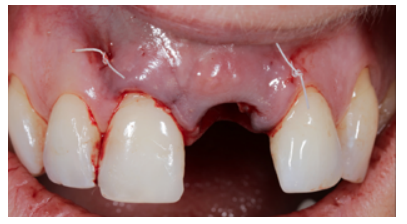

The recipient area was prepared for the approach using the pouch and tunnel technique. A full-thickness incision was made through the vestibular region of the alveolus resulting from the extraction. This fan incision was made with the use of a crescent knife and tunneller. The corona region of the incision was made at full thickness, but the mesial and distal region that compromised the inserted mucosa of teeth 22 and 11 were made at partial thickness; this same plane was maintained in the apical region of the ULCI area.

The donor area was then approached, for which a graft was taken that comprised epithelial tissue and connective tissue (free gingival graft), approximately 2.5 mm thick from the palatal region of the left hemimaxilla, encompassing the premolar and molar region of this zone. This approach was chosen due to the greater guarantees regarding the quality of the connective tissue graft (CTG) when its de-epithelialisation takes place outside the mouth due to the maintenance of the lamina propria.

Due to a 2 mm gingival recession in the URCI, the CTG obtained was of sufficient size to encompass the region of this tooth and to be able to treat this recession simultaneously with the OII procedure. It was adapted to the recipient region with a 5.0 polytetrafluorethylene (PTFE) suture with mesial and distal fixation points, which guaranteed proper vascularisation of the graft (Figures 14A, 14B and 14C).